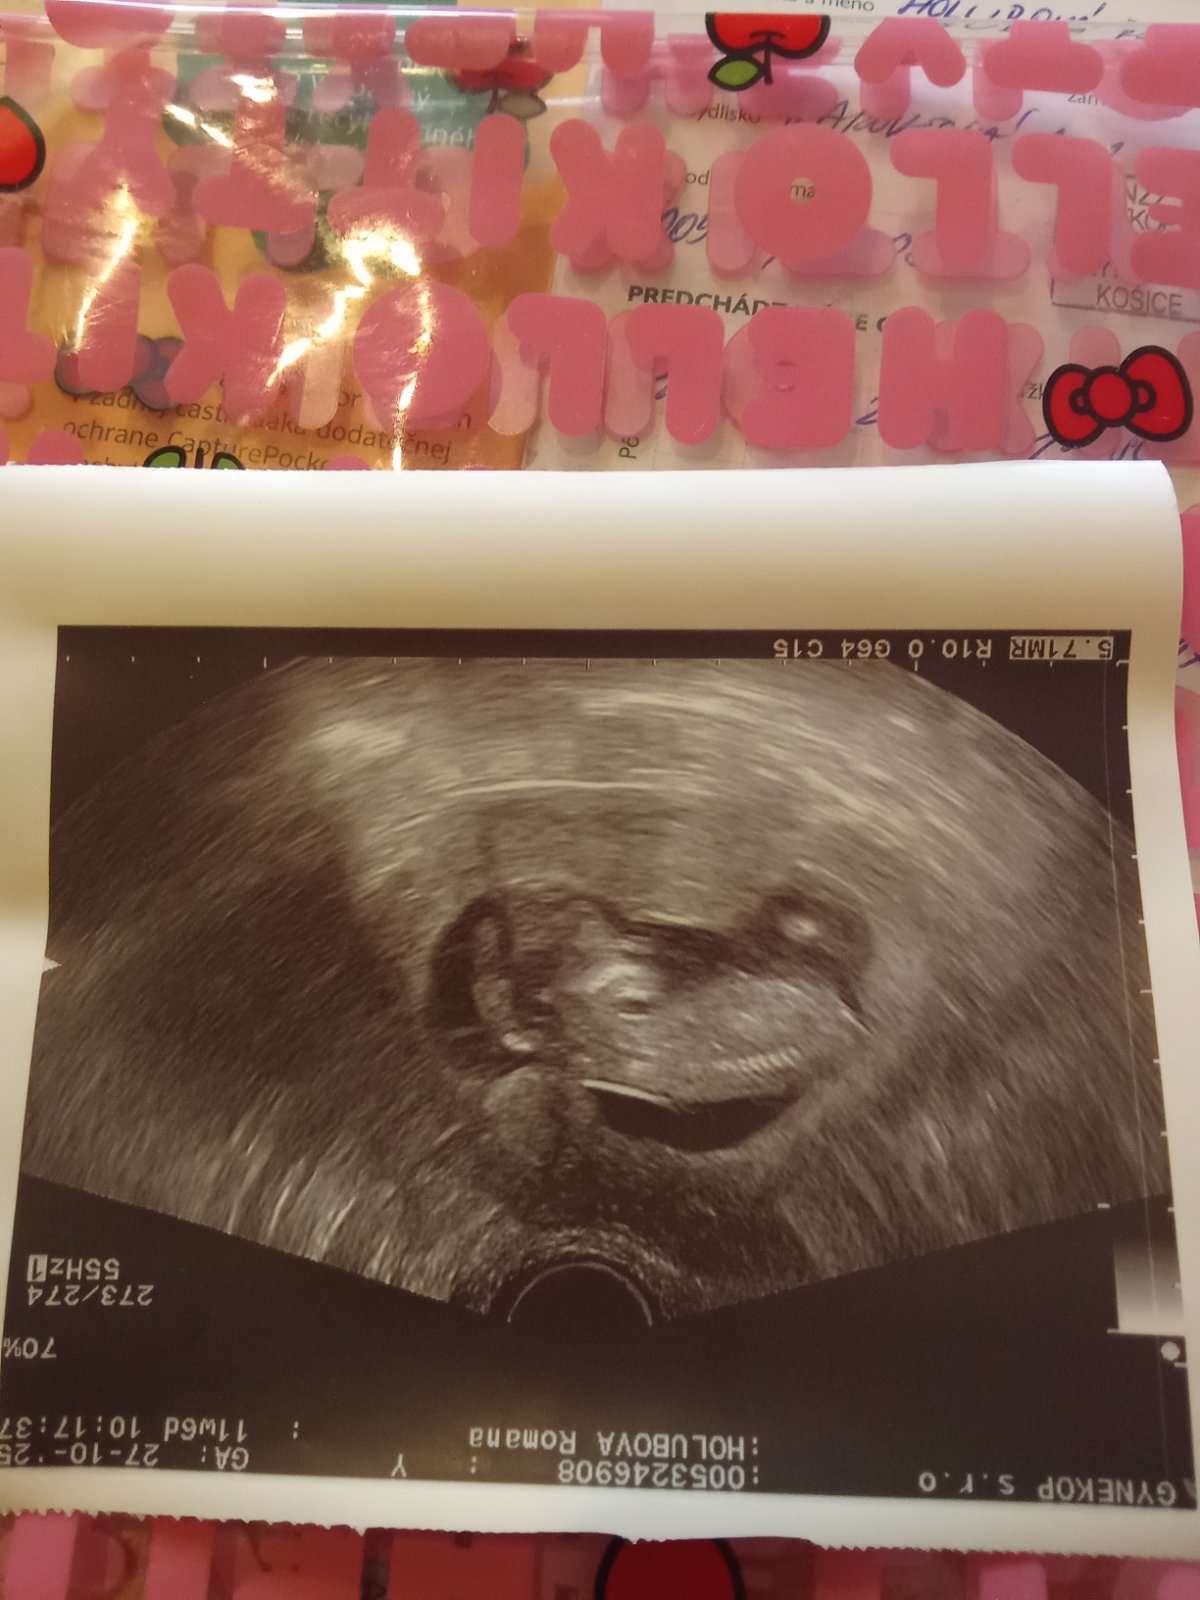

Čakáme podľa ultrazvuku chlapca alebo dievča?

@romana2022 v 12 týždni ešte nie sú dovyvinute pohlavné orgány na správne rozlíšenie 🫣

Da sa to urcit,ale chce to lepsiu foto.Nalavo je hlavicka?Ak ano,ak sa na to dobre pozeram a nalavo je hlava tak to z tejto fotky neurcime.

Vazne z tejto fotky? Pozri sa na tuto fotku sama a zhodnot, ci tam vidis chlapca alebo dievca. Ved ani ziaden lekar by z tejto fotky nedokazal urcit pohlavie.

Podla hlavicky, cela a brady a tejto teorie, je to dievcatko... ale aj moj syn bol taky krasny a je proste chlapcek s jemnymi crtami 😂

Si robíš srandu, že? 🙂 Veď z tejto foto je zrejmé len to, že je to bábätko, z tohto pohlavie neurčí snáď ani jasnovidec 🙂

Pokial nevedel určiť lekár, tak my už dupľom nie. Ale hlavne máš tam rodné číslo a meno, tieto osobé údaje nepatria na MK. A prvé určenie pohlavia nemusí byť presné, veľa ženám sa potvrdilo na 100% až pri ďalšom skríningu alebo sone,ked bolo bábo dobre otočené.

Si v 12tt. Ak ti to nedokazal povedat lekar, tak my podla jednej 2D fotky naozaj nevieme urcit pohlavie. V 12tt castokrat si lekar netrufne a to to tak pozera z kazdeho uhla...